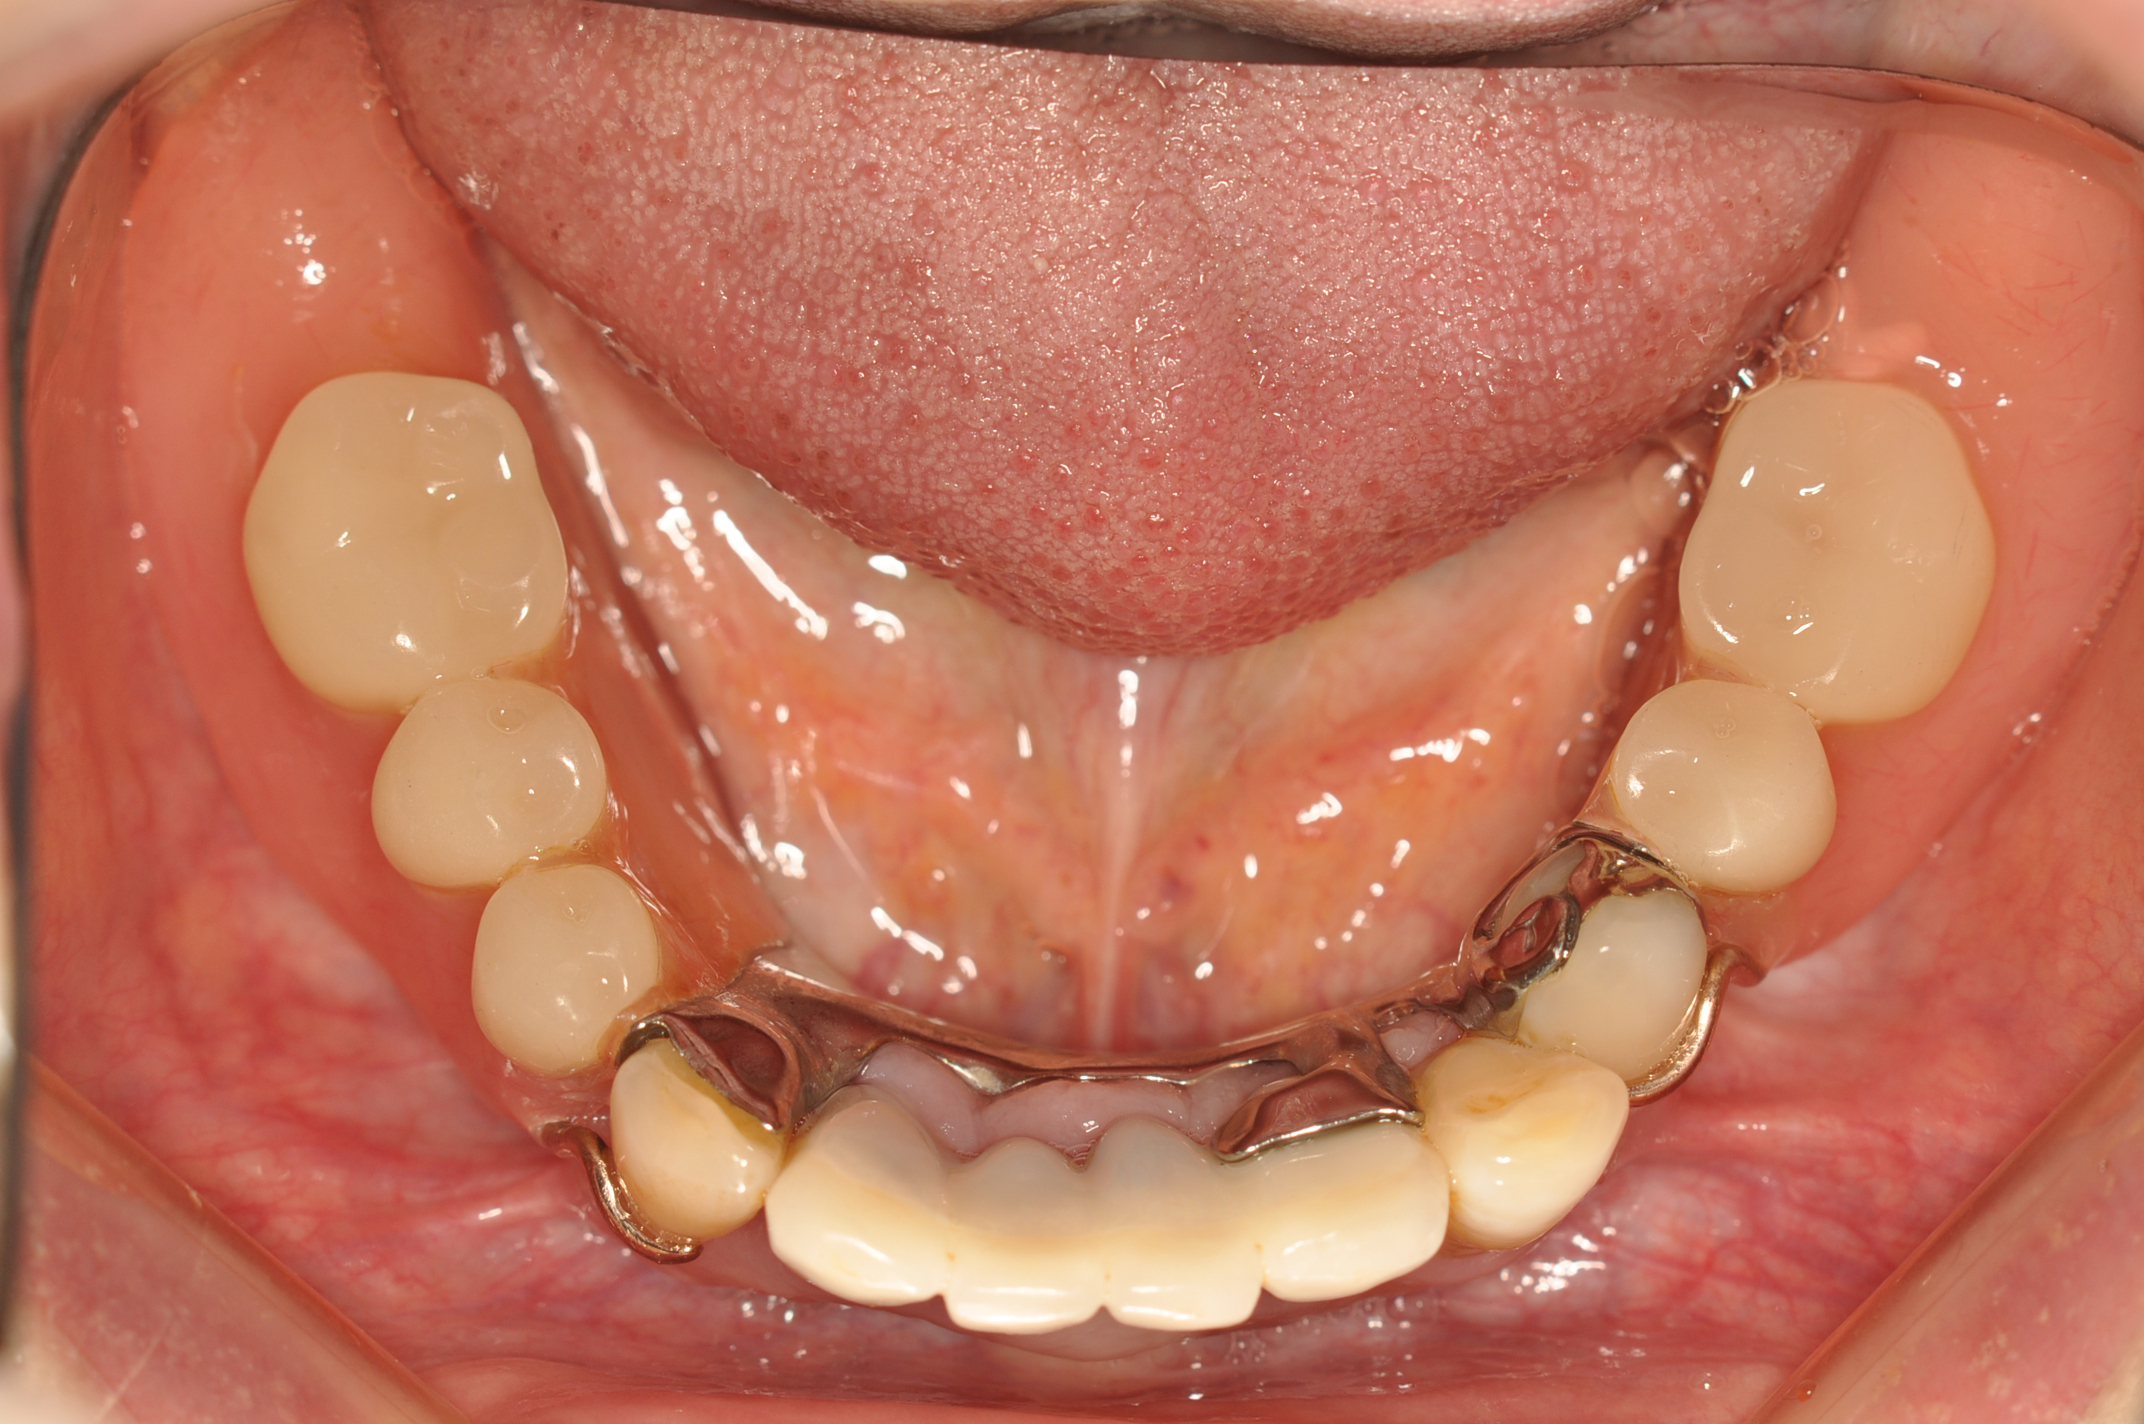

50代女性 部分義歯で対応した重度歯周病症例

娘さんがHPで安藤歯科を探していただいたそうです。義歯が入っているように見えない事が治療条件でした。

試適時の咬みわせチェックの写真です。装着時も咬合器にリマウントしてチェックします。